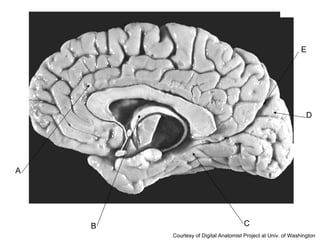

A B C D E Courtesy of Digital Anatomist Project at Univ. of Washington

Answer Key A: cingulate gyrus  B: fornix C: parahippocampal gyrus D: cuneus E: parieto-occipital fissure